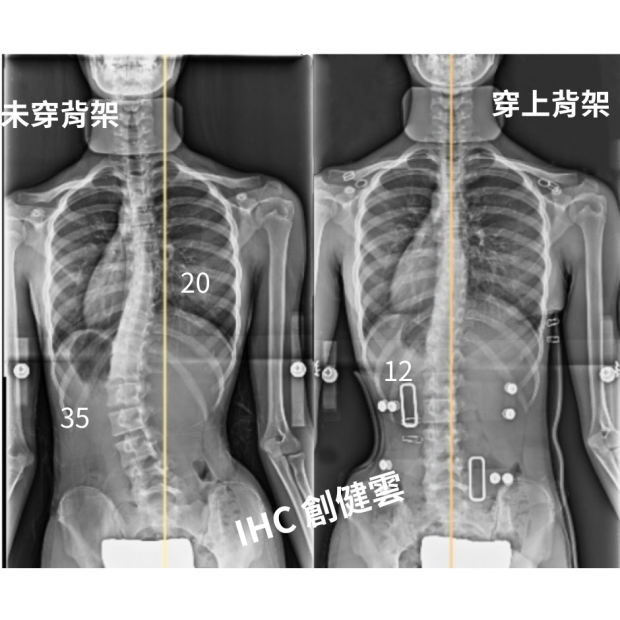

13歲女孩,胸彎31度腰彎44度

13歲女孩,胸彎31度腰彎44度 穿上背架後立即矯正效果